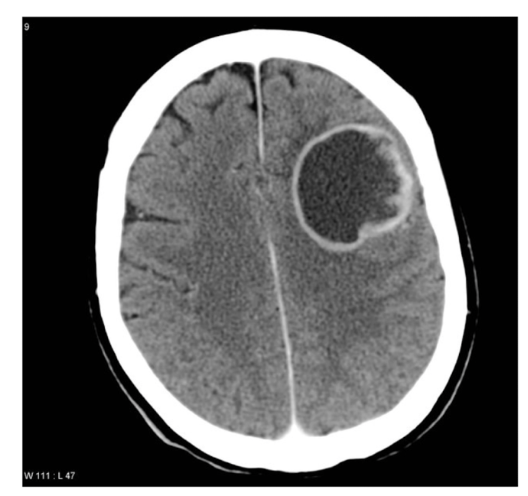

What is the protocol + pathology?

• CT non con brain

• Intraparenchymal

haemorrhage: brain bleed within the brain parenchyma

• Hyperattenuating mass posteriorly in the occipital lobe

• Midline shift

• Adjacent oedema.

Scan + pathology?

• Non con CT

• Path = primary brain tumour

• Adjacent oedema

• Double ring sign

• Contrast phase should be

done to see if tumour is vascular

CT protocol + Pathology?

• Brain C-

• Abscess: fluid filled pockets of infection within the brain parenchyma

• Ring like structure where the hypodense inner ring is pus and the hyperattenuating outer ring is other fluid.

• Adjacent phasogenic oedema.